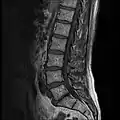

MRI lumbar spine with degeneration (sagittal T2 FRFSE)

MRI lumbar spine with degeneration (sagittal T1 FSE)

MRI lumbar spine with degeneration (sagittal FAST STIR)- MRI lumbar spine pre-hemilaminectomy (sagittal T2 FRFSE)